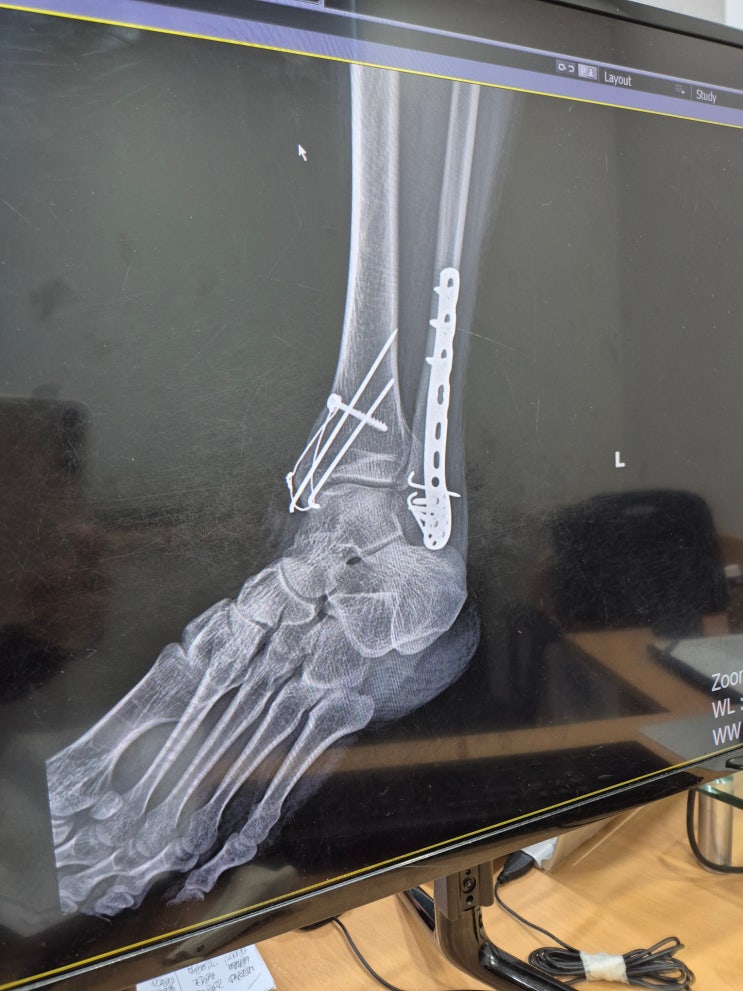

삼복사골절 수술 84일차 - 주치의 병원 방문

삼복사 골절 수술 84일차 한달만에 수술한 병원을 찾아갔다. 병원을 갈때마다 느끼는 거지만, 정말 다치는 ...